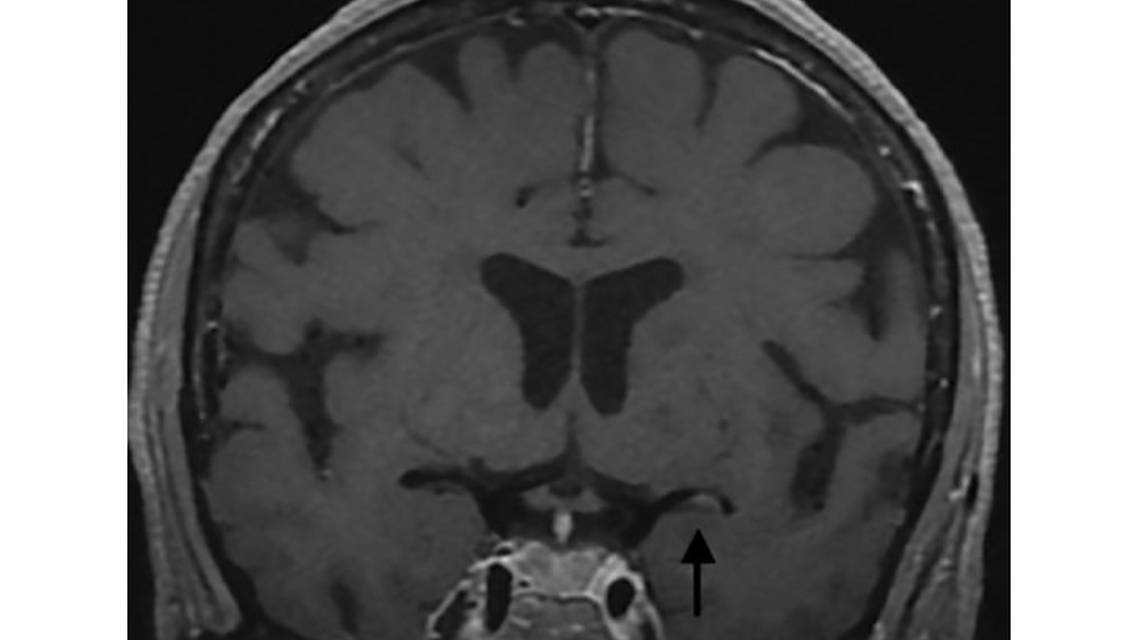

A large group of pathologies that causes vessel wall inflammation comprise vasculitis. On MR-VWI, vasculitis appears as smooth circumferential homogeneous thickening, and enhancement can be multifocal (Figure 2). Enhancement can also extend beyond the vessel wall and into the perivascular soft tissues. Depending on the cause, vasculitis can affect small, medium, and large vessels. Post contrast images demonstrate a tram-track appearance when viewing the vessel in a parallel plane and as a donut when viewing en face.

Transient Cerebral Arteriopathy

The most common type of arteriopathy and a leading cause of acute ischemic strokes in children,15 transient cerebral arteriopathy (TCA) is an inflammatory arteriopathy involving the distal internal carotid artery and its proximal branches, commonly the middle cerebral artery (MCA).16 The main differential to consider is dissection, a distinction that has been difficult to make on imaging before the advent of MR-VMI. TCA demonstrates areas of circumferential and concentric wall thickening and enhancement similar to vasculitis but has a more classic vascular distribution of the internal cerebral artery (ICA) and proximal vessels at the circle of Willis (Figure 2). Earlier studies suggest that the degree of enhancement may also predict disease outcome. Stronger initial enhancement on MR-VWI is typically associated with progression of disease whereas little or no enhancement usually occurs with milder clinical symptoms.17